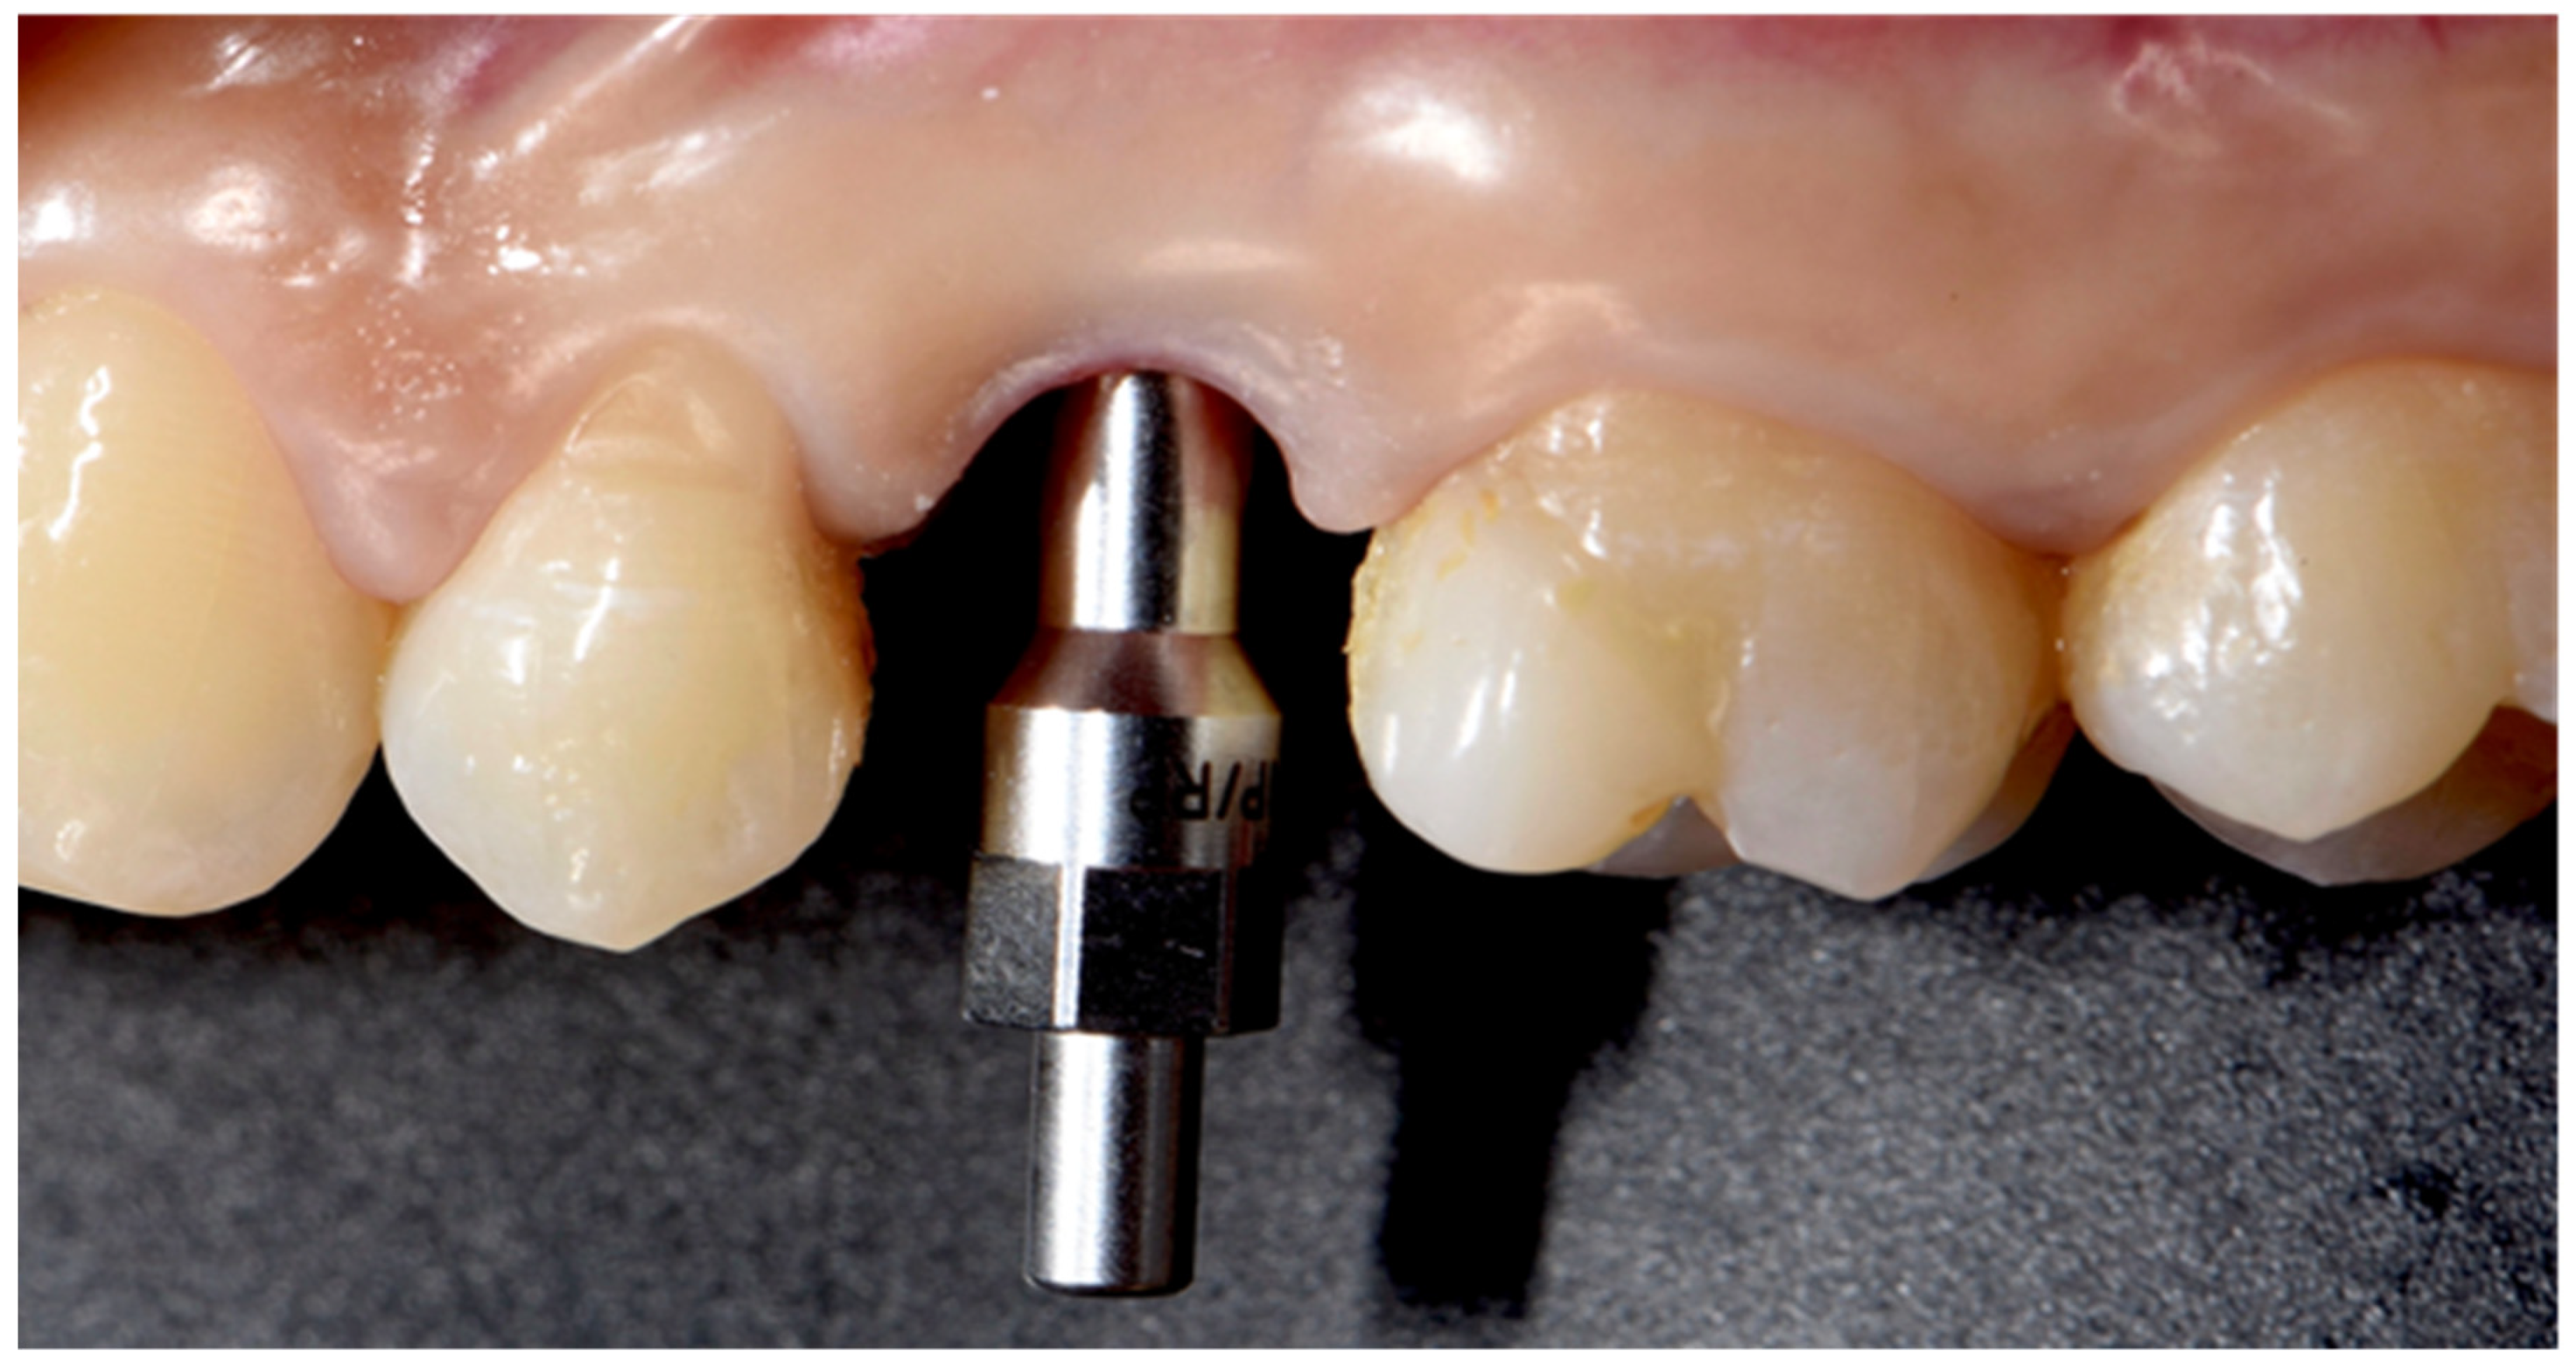

2. Results

2.1. Incidence of Implants Fracture

2.2. Risk Factors for Implants Fracture